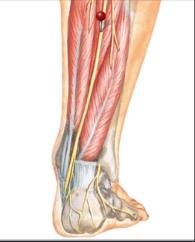

The red pins in the bottom picture point out the nerves in the top pictures. As you can see different nerves travel to different parts of the foot, top, bottom, sides and toes. By isolating the exact location of neuropathy we can isolate the nerve involved.

Diagrams courtesy of Netter's Anatomy